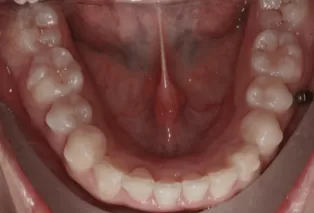

Femme, 25 ans. Plainte principale: dents saillantes et mal alignées, nécessitant un traitement orthodontique.

Avant le traitement

Photos intra-orales